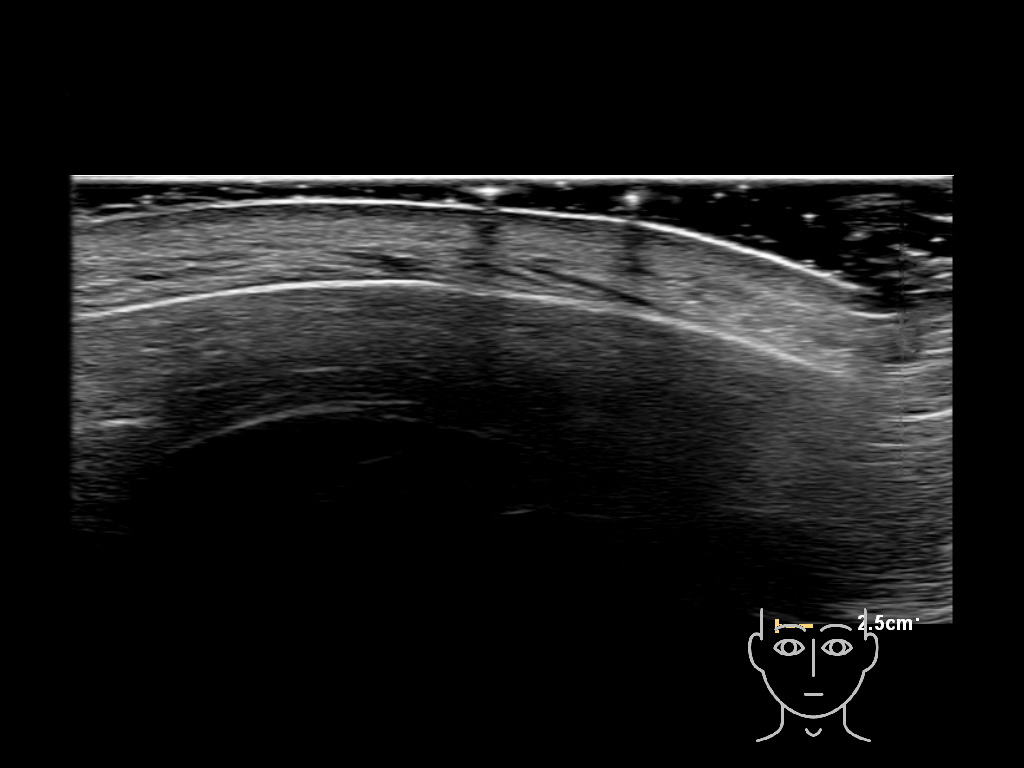

In this section you will learn more about the different layers of the face with the use of ultrasound. When you click on the secondary ultrasound image, you will see the different structures as an overlay. This will help to train yourself to recognize the different layers of the face.

Study the first image to recognize the different layers. If you are sure about the layers, swipe to the second image to view the answer (if applicable).